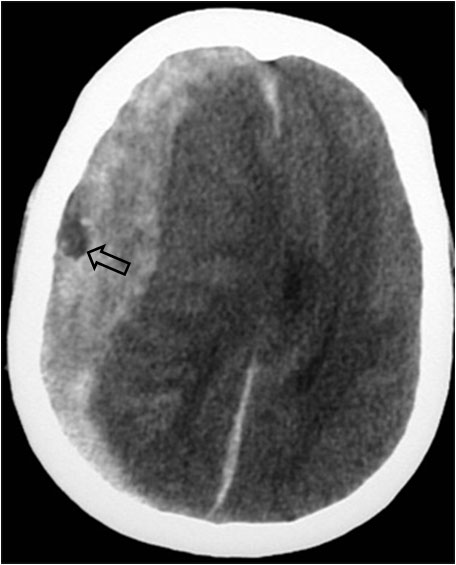

SIGNO DEL PSEUDODELTA

Hemorragia alrededor del seno longitudinal (flecha) en un paciente con TCE. A la derecha pueden verse hematomas subdurales en ambas convexidades -que comprimen el sistema ventricular- y un hematoma subdural de la hoz.

Puede verse un signo pseudodelta en TC sin contraste en pacientes con hemorragia subaracnoidea o subdural (con frecuencia tras traumatismo craneo-encefálico) o con empiema subdural alrededor del seno sagital o longitudinal.

La imagen es similar a la del signo del delta vacío, pero el signo del pseudodelta se ve en estudios sin contraste. La hipodensidad central corresponde a la sangre que circula por el seno sagital superior mientras que la hiperdensidad triangular periférica es debida a la hemorragia subdural o subaracnoidea aguda o a la infección meníngea.